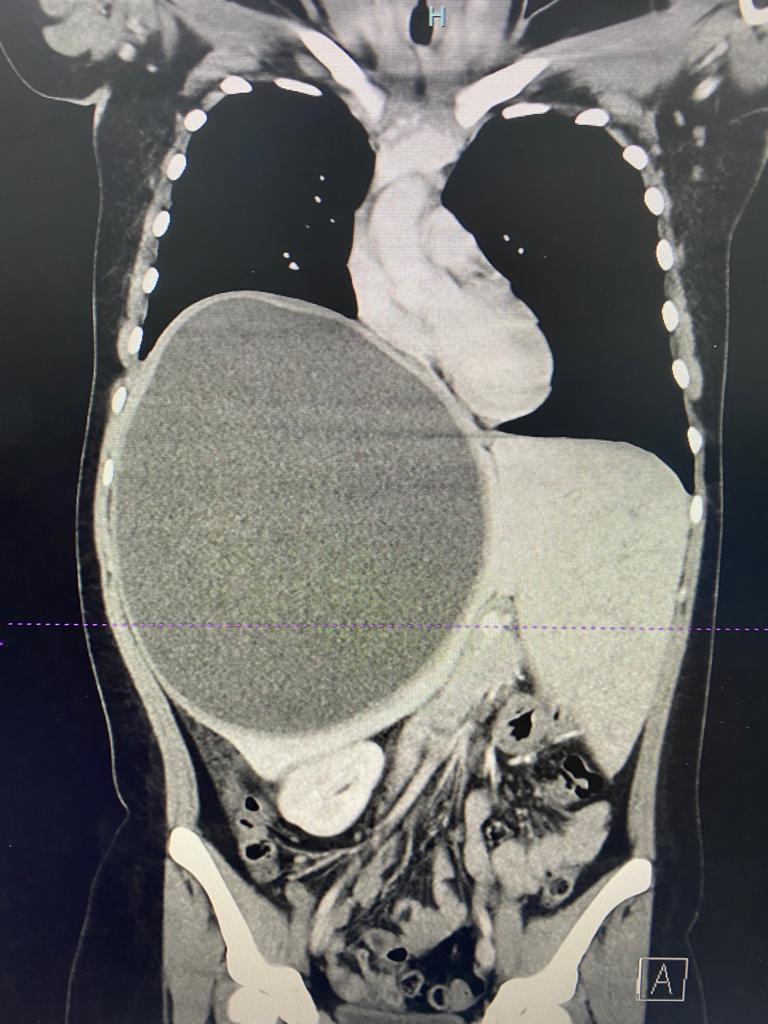

Imágenes y Cirugía

Yousef Allaoua Moussaoui, Enrique Ovejero Merino, Eduardo Serrano Yébenes, Diego Martín Córdova García

Marcelo Felipe Parra, Jose Angel Gamboa, Humberto Lopez Yunnissi, Patricio Olivares Pardo